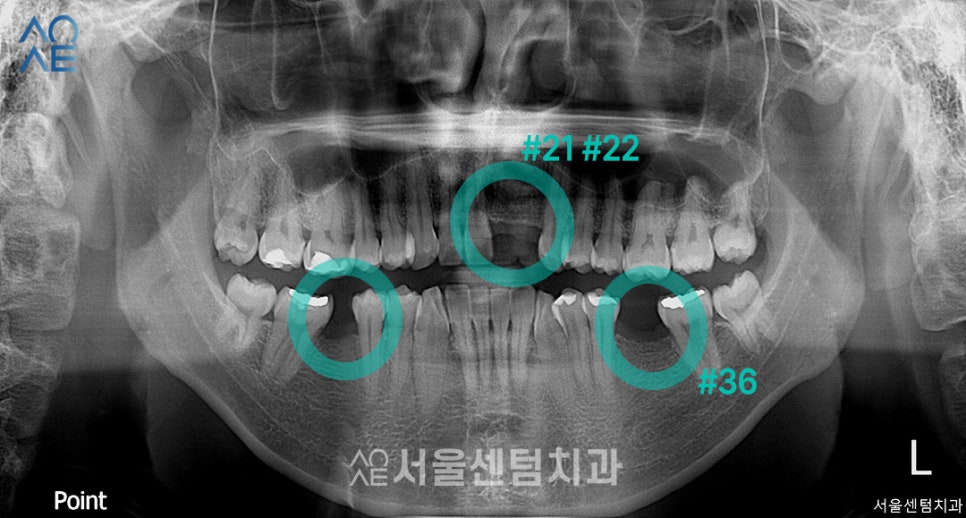

| (1) 현 상태🔹 상실한 치아는 총 4개 (앞니는 2개)🔹 전체적으로 잇몸이 조금 내려가있음🔹 충치치료도 필요해보임 |

| (2) 임플란트 수술 계획🔹왼쪽 아래 어금니부터 진행🔹4주 후 왼쪽 앞니쪽도 수술 진행 |